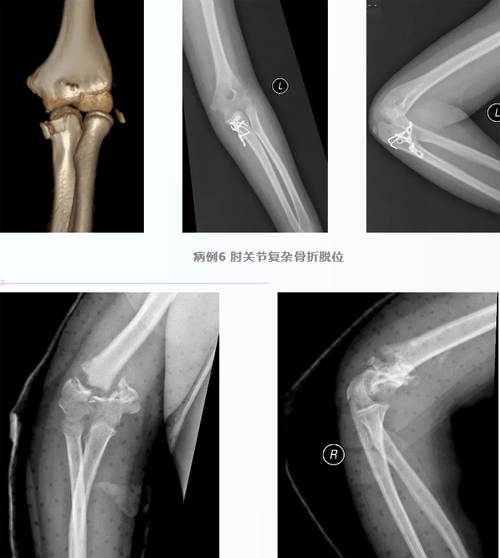

病例7 肱骨髁间骨折术后肘关节僵硬

松解后